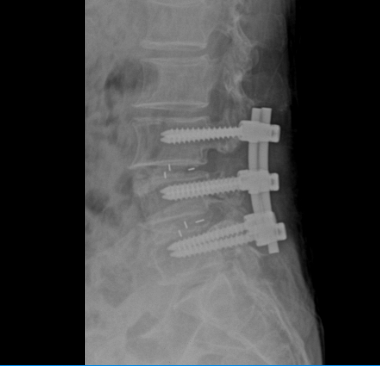

Qua thăm khám và các chỉ định cận lâm sàng cần thiết, bác sĩ Khoa Ngoại Chấn thương chỉnh hình chẩn đoán người bệnh bị thoát vị đĩa đệm L34, L45 gây hẹp nặng ống sống thắt lưng và chèn ép rễ thần kinh ngang mức. Bệnh nhân được chỉ định phẫu thuật cố định cột sống, giải ép thần kinh và hàn xương liên thân đốt L34, L45.

Ca phẫu thuật được tiến hành thuận lợi, sau phẫu thuật bệnh nhân hết triệu chứng đau nhức 2 chân và đã được hướng dẫn tập Phục hồi chức năng ngay sau mổ. Theo bác sĩ Nguyễn Mạnh Thuần – Khoa Ngoại chấn thương chỉnh hình, thoát vị đĩa đệm gây chèn ép rễ thần kinh, tủy sống thì phẫu thuật giải ép, ghép xương liên thân đốt và cố định cột sống là phẫu thuật triệt để và ổn định nhất cho người bệnh.